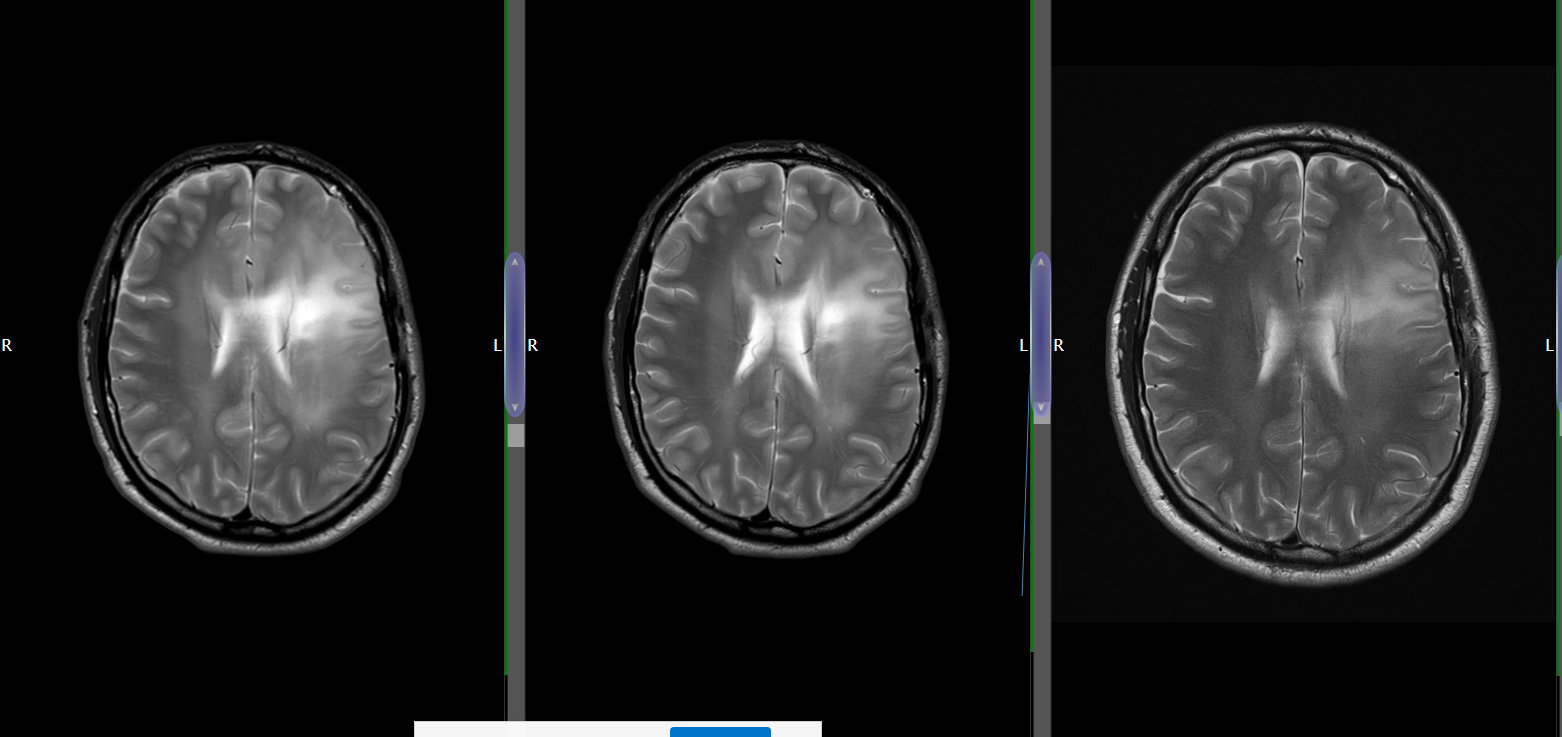

After a road traffic accident, a pear-sized Glioma–a type of brain cancer was discovered as an unexpected and unwelcome guest in my head

The Story, So far in pictures…